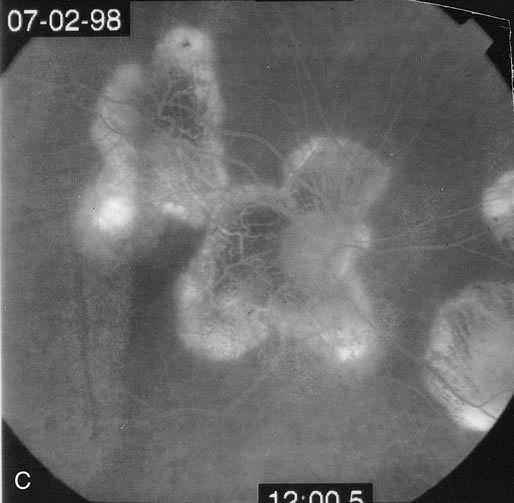

The classic findings in the acute cases are lesions of variable size that are hypofluorescent in the early phase of the fluorescein angiogram. In the late phases of the angiogram there is hyperfluorescence of the lesions. In the late phases, there also may be leakage from the disc as well, and there also may be staining of the retinal vessels because of the vasculitis. With resolution of the disease, there still may be a mottled pattern of fluorescence correlating with the areas of pigment clumping and pigment atrophy (Fig. 8).

Fig. 8. A. Early fundus angiogram showing hypofluorescence of the acute posterior multifocal placoid pigment epitheliopathy (APMPPE) lesions. B. Later stage of the angiogram showing staining of the APMPPE lesions.